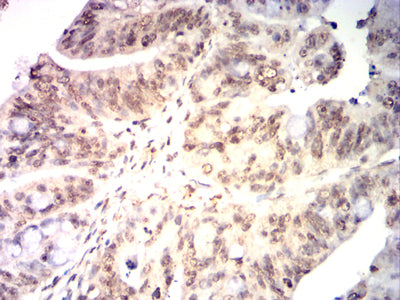

Immunohistochemical analysis of paraffin-embedded human ovarian cancer tissues using KMT2A mouse mAb with DAB staining.